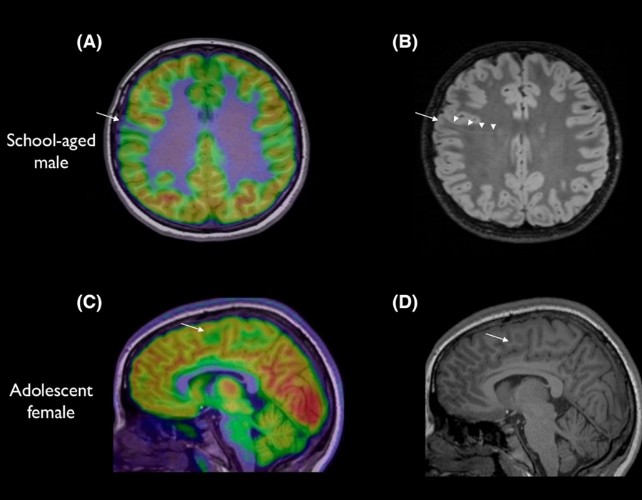

在儿童癫痫诊治中,一项澳大利亚研究展示了一个人工智能工具,能够检测极小、极易错过的脑部畸形,帮助患者更快获得可能改变命运的手术。 专家指出,癫痫的病因多样,但约有三成病例与脑部结构异常相关。这些异常往往在MRI上被漏看,尤其是最小的病灶,常隐藏在脑回褶皱的深处。

由墨尔本皇家儿童医院的 Emma Macdonald-Laurs 率队,研究人员让AI工具学习儿童脑部影像,以发现直径如蓝莓般大小甚至更小的病变。 她说:‘工具并不替代放射科医生或癫痫医生,而是像侦探一样,帮助我们更快拼凑线索,从而提供可能改变生活的手术。’

研究对象包括皮层发育不良和局灶性癫痫患者。结果显示,80%的孩子在研究中此前的MRI都显示为正常。 当研究人员将AI结合MRI与另一种成像技术 PET 时,诊断的成功率分别达到94%和91%(分组数据)。